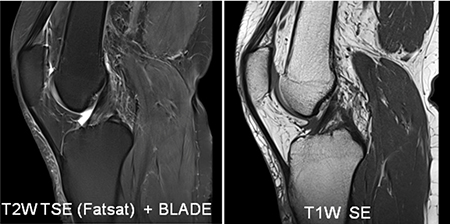

<SIEMENS社製MAGNETOM skyra3.0テスラ(T)MRIのご紹介>

3.0テスラの強い磁場で検査することにより、より強い信号が得られるため情報量が多く、より高分解能(高画質)な画像、より短時間撮影が可能となりました。

多彩な専用コイルで高画質

頭部や脊椎、乳房専用コイル、肩関節専用、膝関節専用、手指関節専用など撮像部位に応じた多彩なコイルを用意しています。

[膝関節撮像例]

“IDEAL” &“ FLEX”

従来脂肪抑制が困難な領域、部位においても均一な脂肪抑制画像を提供します。

頸部や金属固定金具などの脂肪抑制が困難な場合でも、“IDEAL”「3ポイントDixon法でより正確に」磁場抑制むらのない、均一な脂肪抑制画像を得ることができます。LAVAとの組み合わせによる“LAVA-FLEX”「2ポイントDixon法」でより高速にダイナミック撮像、息止め撮像で使用可能です。